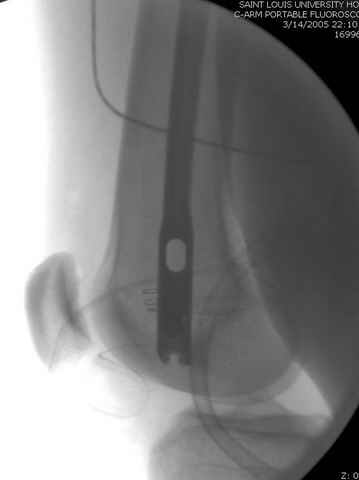

03.14.2005

больному 42, автоавария, политравма, открытая черепномозговая травма, безсознании, открытый перелом бедра, размозжение мягких тканей, дефект кожи на передней поверхности бедра около 13 см2 от ожога, компартмент синдром.

По поводу открытого перелома больной ургентно взят на ретроградное интрамедулярное штифтование, после рутинного дебрайдмента и фасциотомии на бедре и на голени.

интраоперационные

|